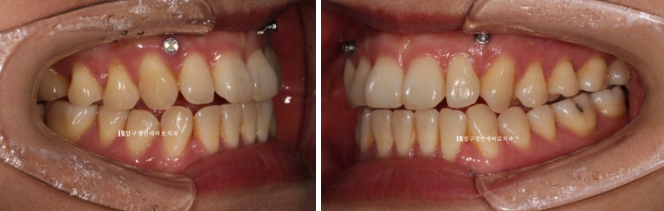

23.01~24.07

인비절라인 투명교정과 양악수술의 조합은 좋은 결과가 나옵니다.

교정기간으로는 보통 1년 내외 생각하시면 됩니다.

이 환자분도 첫 장치를 끼신 23년 6월부터 24년 7월까지 총 1년 1개월이 걸렸고

중간에 재제작 하느라 장치를 기다리시던 한달을 빼면 실제 치료하신 기간은 1년입니다.